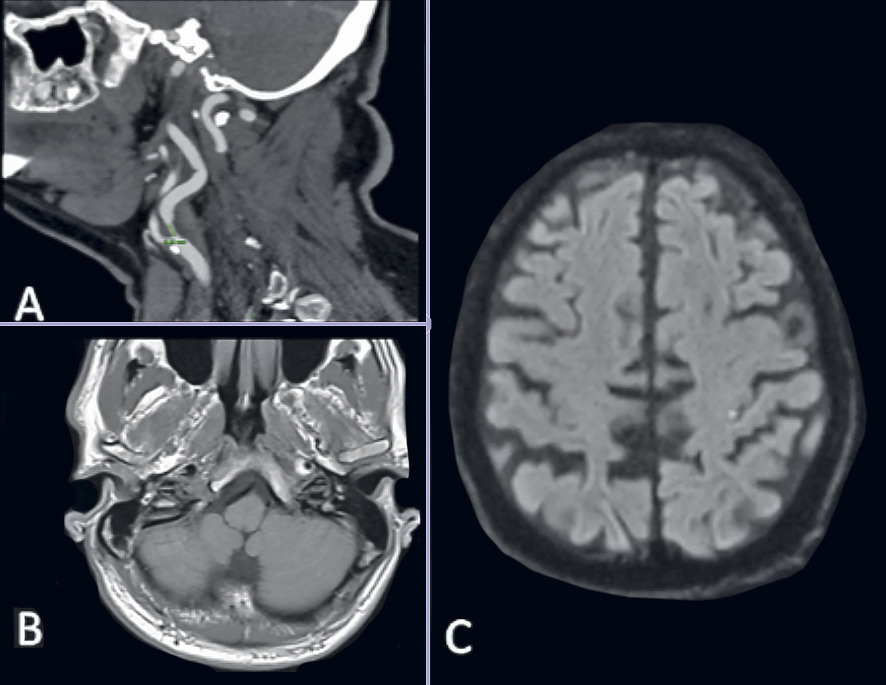

Un athérome des troncs supra-aortiques (TSA) [rétrécissement > 50 %] est considéré comme une cause d’AIT dans le territoire vasculaire concerné. Il peut être mis en évidence par doppler, angio-IRM ou angioscanner (fig. 1A). Une sténose carotidienne de plus de 50 % dans le territoire concerné par l’AIT (par exemple hémiplégie gauche transitoire associée à une sténose carotidienne droite) fait discuter une chirurgie en semi-urgence (< 15 jours) car le risque de récidive est élevé (5 % à 30 jours). Elle est retrouvée chez plus de 15 % des patients explorés (fig. 1A).1 Il est donc impératif de pratiquer chez tous les patients suspects d’AIT une imagerie des vaisseaux extracrâniens.

Une dissection des troncs supra-aortiques doit être suspectée chez un sujet jeune se plaignant de céphalées ou de cervicalgies, même minimes. Ce tableau doit faire prescrire une IRM Fat-Sat (saturation de graisse et des flux vasculaires) des vaisseaux extracrâniens (fig. 1B).

Les scores de gravité prennent en compte la probabilité d’une origine vasculaire à l’événement neurologique, l’évaluation du parenchyme cérébral et des vaisseaux cervico-encéphaliques. Ils peuvent être établis au terme du bilan étiologique. À l’heure actuelle, le plus complet est le score ABCD3I (non validé ; tableau).5 Une lésion récente en IRM cérébrale est associée à un risque de récidive accru (fig. 1C). Ce dernier est estimé à 4,8 % à 7 jours de l’événement initial si le score ABCD3I est ≥ 8. Chez les patients à haut risque de récidive, une hospitalisation est préconisée.